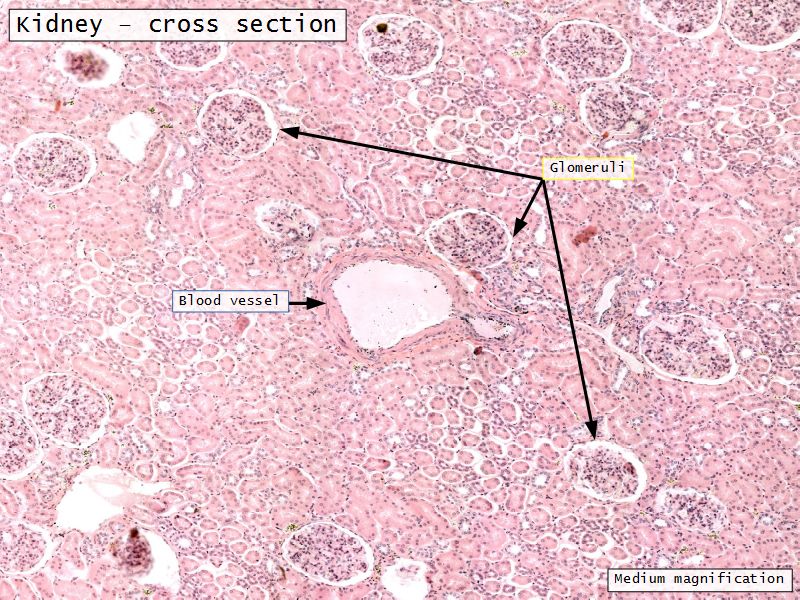

Appearance

- Cortex

- Renal corpuscles

- Convoluted tubules

Renal corpuscle

- Tuft of capillaries

- grow into

- Blind end of nephron

- Several layers of epithelium

- Two sides

- Vascular pole

- Tubular pole

Blood flow

- Efferent arteriole

- Smooth muscle in media

- Capillaries

- Fenestrated

- Afferent arteriole

- Smooth muscle in media